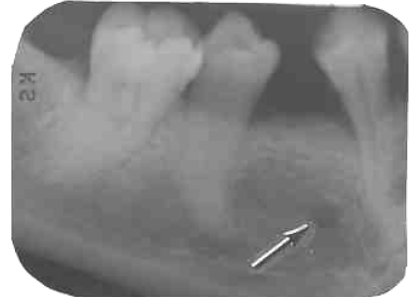

4. What is the anatomical structure indicated by arrow in this radiograph?